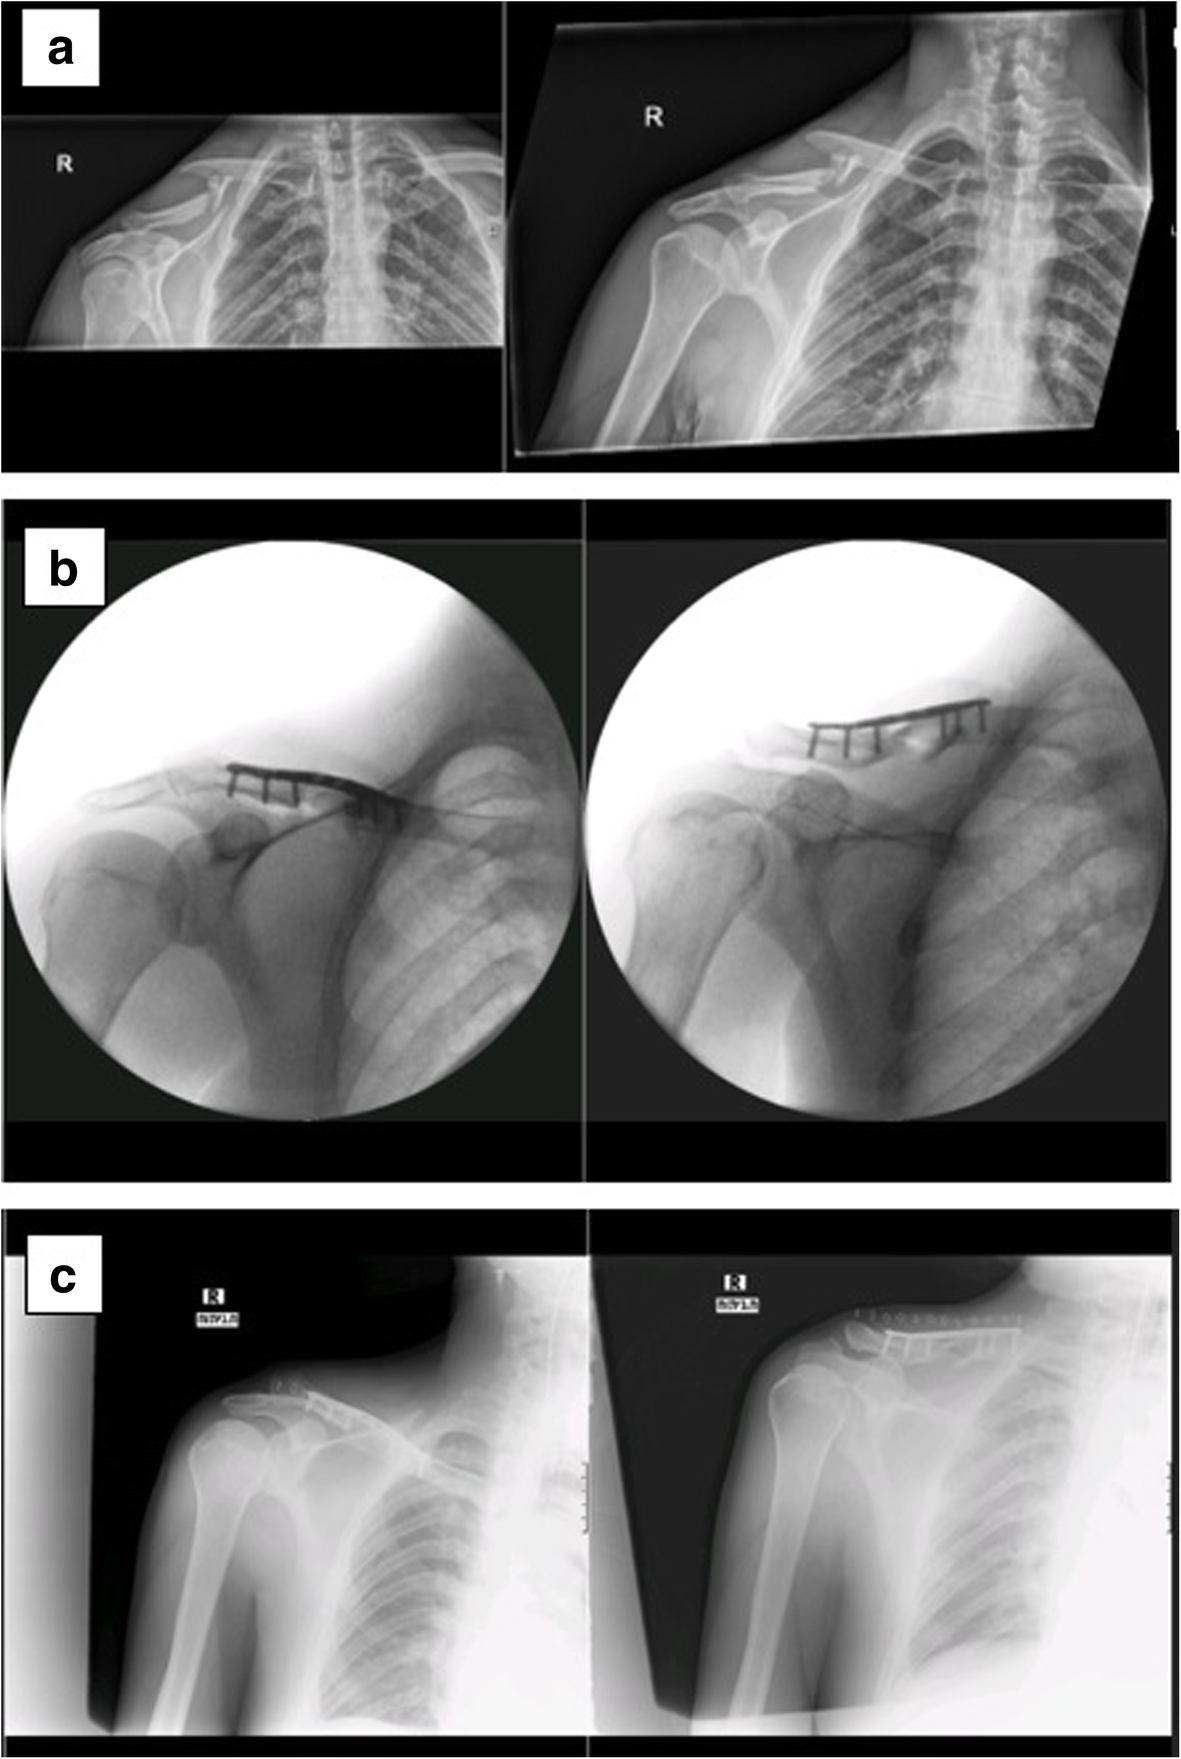

(A) Displaced comminuted midshaft clavicle fracture (Robinson Type 2B2 Midshaft Clavicle Fracture Icd 10 The icd code s420 is used to code clavicle fracture. Icd 10 code for fracture of clavicle. Icd 10 code for displaced fracture of shaft of left clavicle, initial encounter for closed fracture. Get free rules, notes, crosswalks, synonyms,. Midshaft clavicle fractures are common traumatic injuries caused by a direct impact to the shoulder girdle and is most commonly seen. Midshaft Clavicle Fracture Icd 10.

a.) Case 1 anteriorposterior (AP) radiograph demonstrating a Midshaft Clavicle Fracture Icd 10 Get free rules, notes, crosswalks, synonyms,. Icd 10 code for fracture of clavicle. A prominent callus is common in children, and parents may require. A clavicle fracture is a bone fracture in the clavicle, or collarbone. Icd 10 code for displaced fracture of shaft of left clavicle, initial encounter for closed fracture. It is often caused by. The icd code. Midshaft Clavicle Fracture Icd 10.

a, b Comminuted displaced midshaft clavicle fracture left with Midshaft Clavicle Fracture Icd 10 A clavicle fracture is a bone fracture in the clavicle, or collarbone. Icd 10 code for fracture of clavicle. Icd 10 code for displaced fracture of shaft of left clavicle, initial encounter for closed fracture. It is often caused by. Get free rules, notes, crosswalks, synonyms,. The icd code s420 is used to code clavicle fracture. Midshaft clavicle fractures are. Midshaft Clavicle Fracture Icd 10.

(a) Left closed comminuted midshaft clavicle fracture; (b) fracture end Midshaft Clavicle Fracture Icd 10 A prominent callus is common in children, and parents may require. A traumatic or pathologic injury to the clavicle in which the continuity of the clavicle is broken. Most clavicle fractures occur in the midshaft and can be treated nonoperatively. Icd 10 code for fracture of clavicle. It is often caused by. A clavicle fracture is a bone fracture in. Midshaft Clavicle Fracture Icd 10.